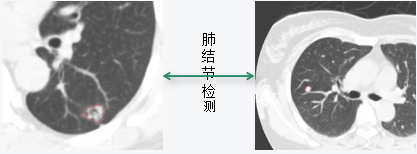

肺

肺癌的发病率和死亡率持续上升。

肺癌在男性肿瘤疾病中已居首位,在女性中仅次于乳腺癌。

我国肺癌患者居世界首位。

有效手段是“早期发现、早期诊断、早期治疗”。

X射线和CT。

肺CAD

肺结节检测

肺结节检测

结节提取:

-------结节检测

-------结节分割

结节定量分析:

结节的CT均值、CT最大值、CT最小值、体积、重量、中心位置像素坐标等信息。

结节随访:

同时观察新旧两套肺CT序列,配准两套数据的结节,评估结节的倍增率和倍增时间。